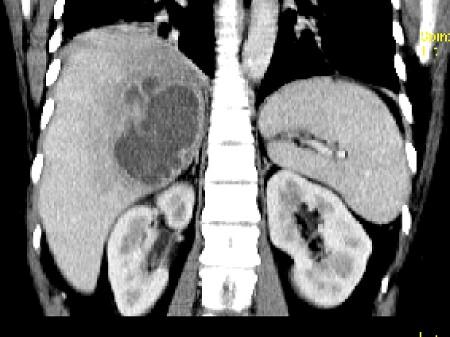

问题 女,36岁,右上腹痛,有发热,白细胞计数升高,CT检查如图,最可能诊断是 ( )

选项 A、肝黄色肉芽肿 B、肝胆管细胞癌 C、肝淋巴管瘤 D、肝脓肿 E、原发性肝癌

答案 D